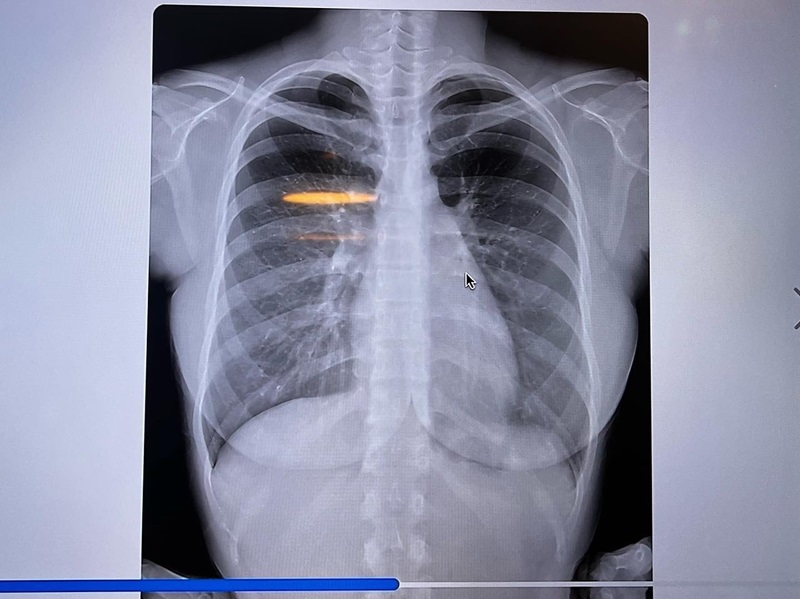

ดาราสาวญี่ปุ่นชื่อดัง เจ้าของหน้าอกคัพ L โดนถามไม่ไหว ของแท้แม่ให้มาไหม คับอกคับใจ โชว์ให้ดูถึงกระดูก ตบ ๆ กันไป

ด้วยความที่หน้าอกของเธอนั้นใหญ่แบบอลังการ ทำให้ดาราสาวสุดแซ่บรายนี้ มักจะเจอแต่คำถามเดิม ๆ อยู่บ่อยครั้ง นั่นคือ "หน้าอกนี้เป็นธรรมชาติ เป็นของแท้หรือเปล่า" จนล่าสุด เมื่อไม่นานมานี้ ฟูมินะ ได้ออกมาโพสต์ภาพยืนยันกันแบบจัดเต็ม ให้เห็นกันถึงไส้ถึงพุงกันเลยทีเดียว

โดยจากภาพเอกซเรย์ดังกล่าว แสดงให้เห็นว่า ไม่มีวัสดุเต้านมเทียม หรือสารแปลกปลอมที่หน้าอกของเธอ จึงพิสูจน์ได้ชัดว่าคัพ L ของเธอ เป็นของแท้แม่ให้มาแน่นอน